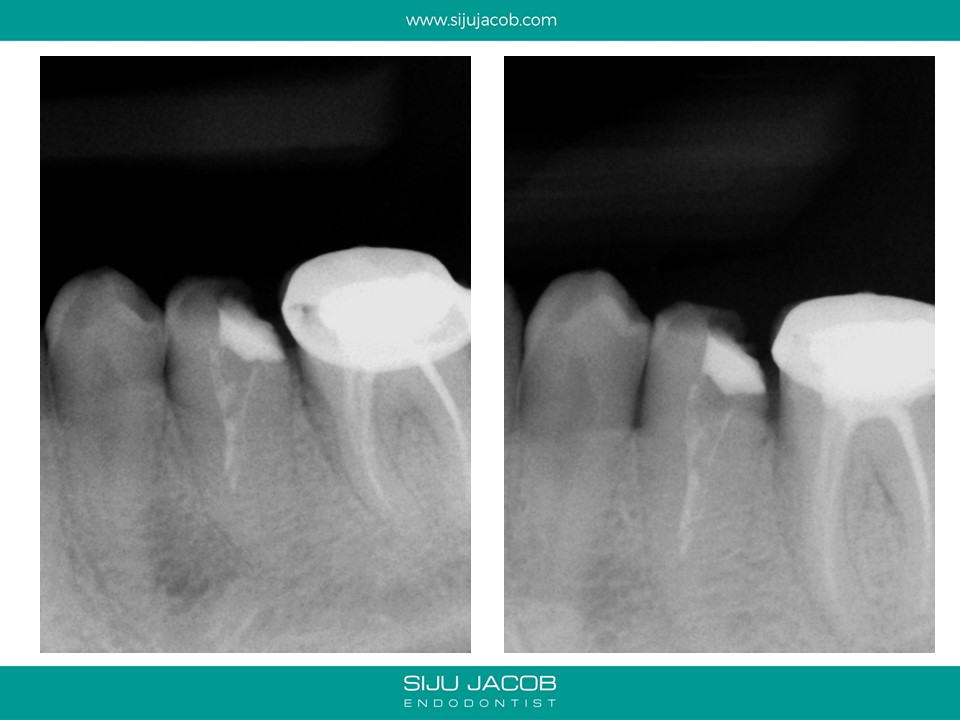

Previous clinician started this case and referred it when the patient continued to have pain. This was a two-rooted mandibular pre-molar with the canals present at a very odd angle and position. It was difficult to clean, shape and pack because the canals were very close to each other. When obturating these canals, I usually down pack one canal, then use a small micro-opener to remove the G.p that usually blocks the second canal and then down pack the second canal.